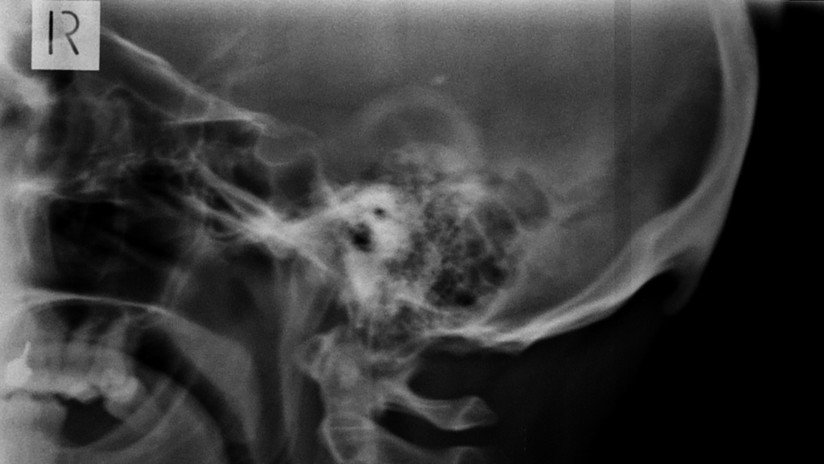

En el hospital, Wang fue diagnosticado con un derrame ocular, también conocido como oclusión arterial retiniana. Esta dolencia sobreviene cuando se forma un coágulo o estrechamiento de los vasos sanguíneos en la retina que le impide enviar señales al cerebro. Como resultado, uno puede quedar ciego permanente si el derrame no se trata de inmediato.

"El bloqueo de las arterias en la retina es repentino y grave, y es la manifestación primaria de la enfermedad ocular que conduce a la ceguera", advirtió el médico, subrayando que para protegerse es importante usar estrategias preventivas.